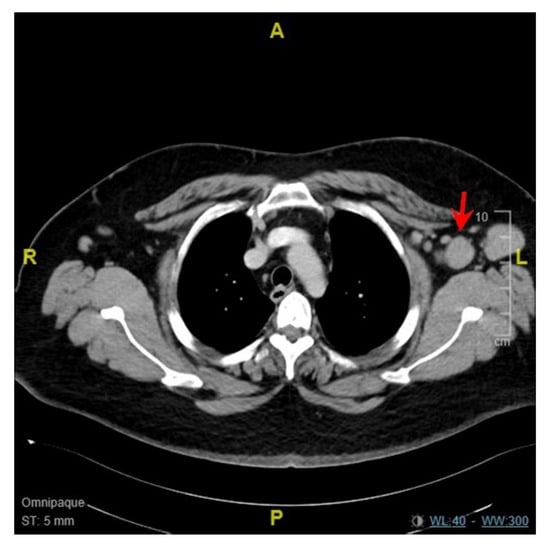

| Our case, patient A | 18 | Female | Pfizer- BioNTech | 35 days | Supraclavicular, subpectoral and axillary | Core biopsy | KFD 2 |